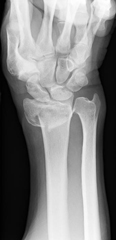

1. 橈骨遠位端骨折

粉砕の強い場合、関節内に骨折が及ぶ場合は手術を行います。プレートを用いた整復固定を行いますが、粉砕の強い場合は創外固定や人工骨充填を併用します。